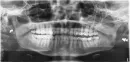

С февраля месяца начала болеть верхняя челюсть. Особенно сильно передние зубы. Ощущение сжатия, как будто горят передние зубы. Депульпировали передний зуб, реагировал на холод сильно. На холоде болеть перестал. Но дискомфорт, не уменьшился совсем. Зуб дальше болит, хоть понимаю, пульпы нет. Но особенно болит по утрам. Чувство сжатия не прошло. Боль выматывает. Что это может быть?

По фото канал зуба пролечен хорошо. Подобные симптомы могут быть связаны с нарушением окклюзионных контактов или перенапряжением мышц от присутствия восьмых зубов.